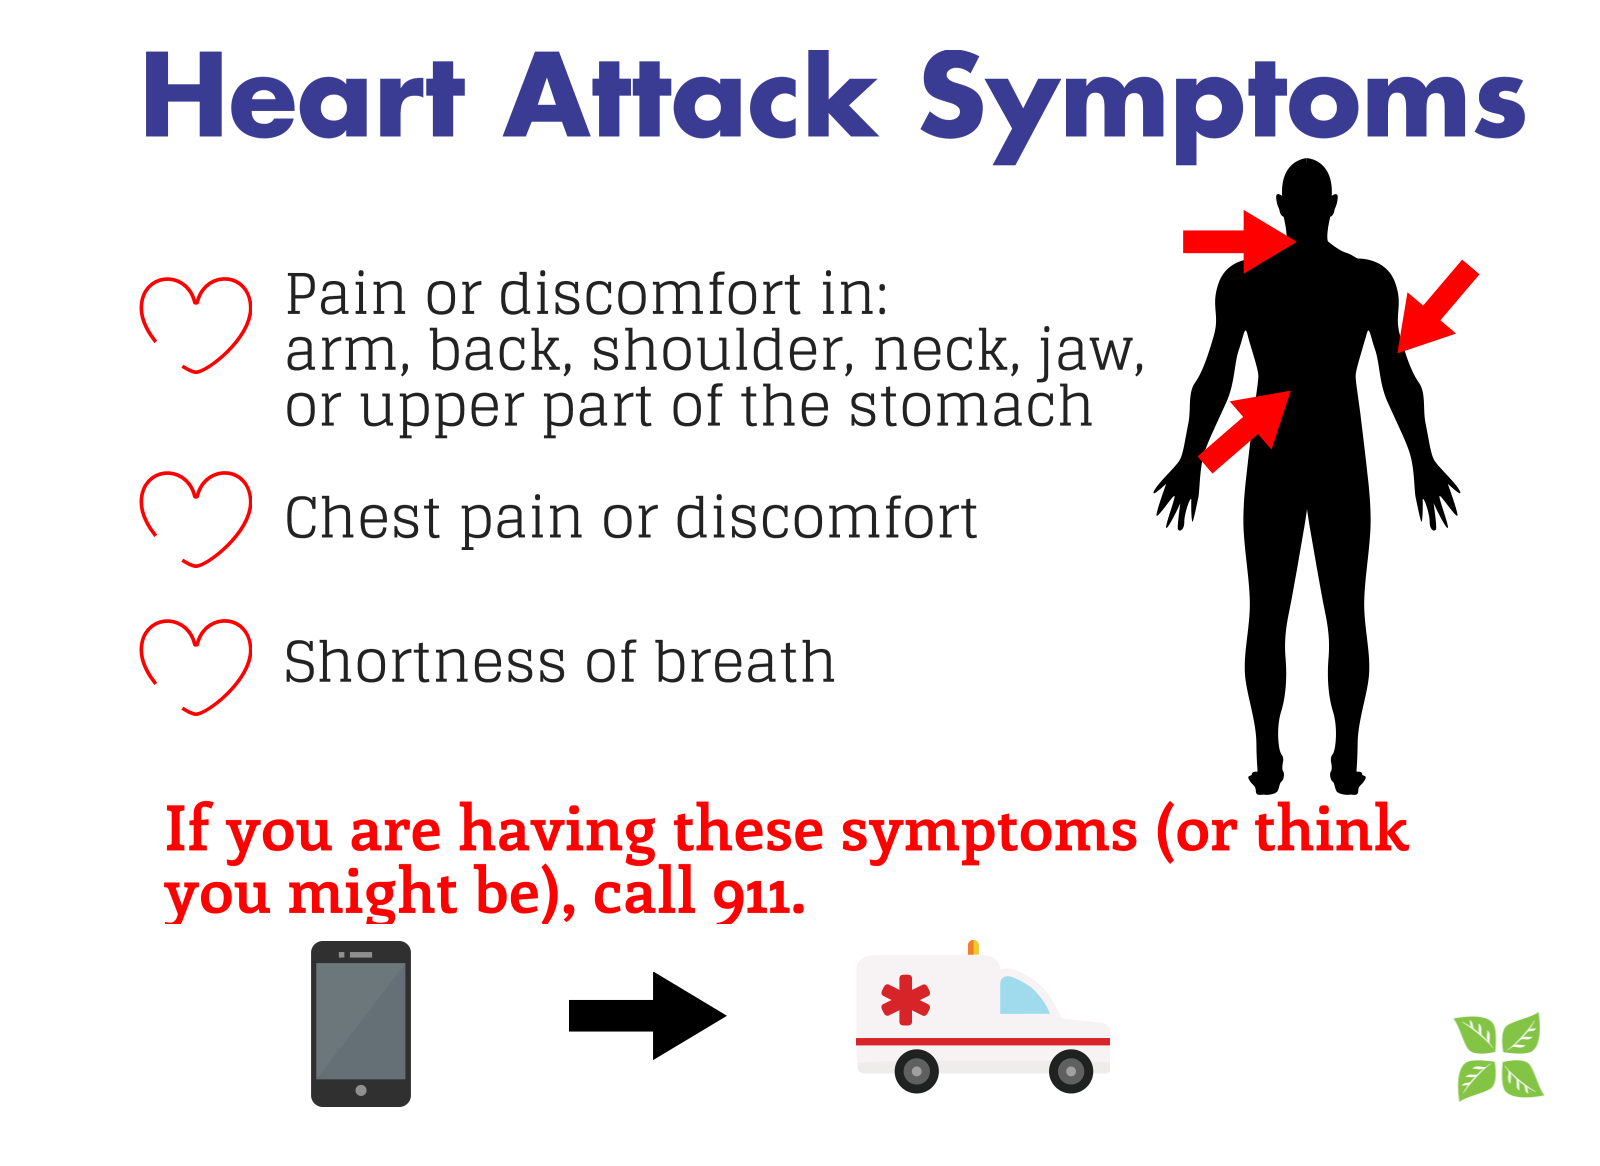

Heart Attack Symptoms

Heart Attack Signs And Symptoms